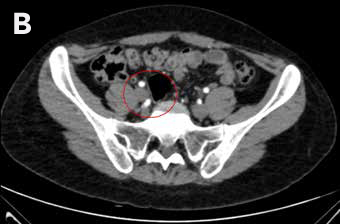

Mujer de 27 años, con antecedente de amenorrea primaria con hábito femenino, mamas Tanner V, escaso vello no terminal axilar y púbico, y que tenía pareja heterosexual y vida sexual normal. Sus exámenes hormonales demostraron testosterona en rango masculino (Tabla 1) y cariograma 46,XY compatible con insensibilidad a andrógenos. La TAC de pelvis mostró ausencia de útero, una imagen ovoidea con densidad de partes blandas de 27 mm de diámetro mayor a nivel de la bifurcación de los vasos iliacos derechos interpretada como ovario normal, y en situación anexial izquierda una masa sólida de 90 mm de diámetro mayor, bien delimitada algo heterogénea sin calcificaciones, sin liquido libre ni adenopatías (Figura 2). Fue sometida a gonadectomía bilateral 4 años antes de la consulta y la biopsia demostró un seminoma espermatocítico de 11 cm asociado a un foco de neoplasia germinal intratubular de 2 mm en la gónada izquierda y un testículo atrófico y fibroso, con epidídimo de aspecto conservado a derecha.